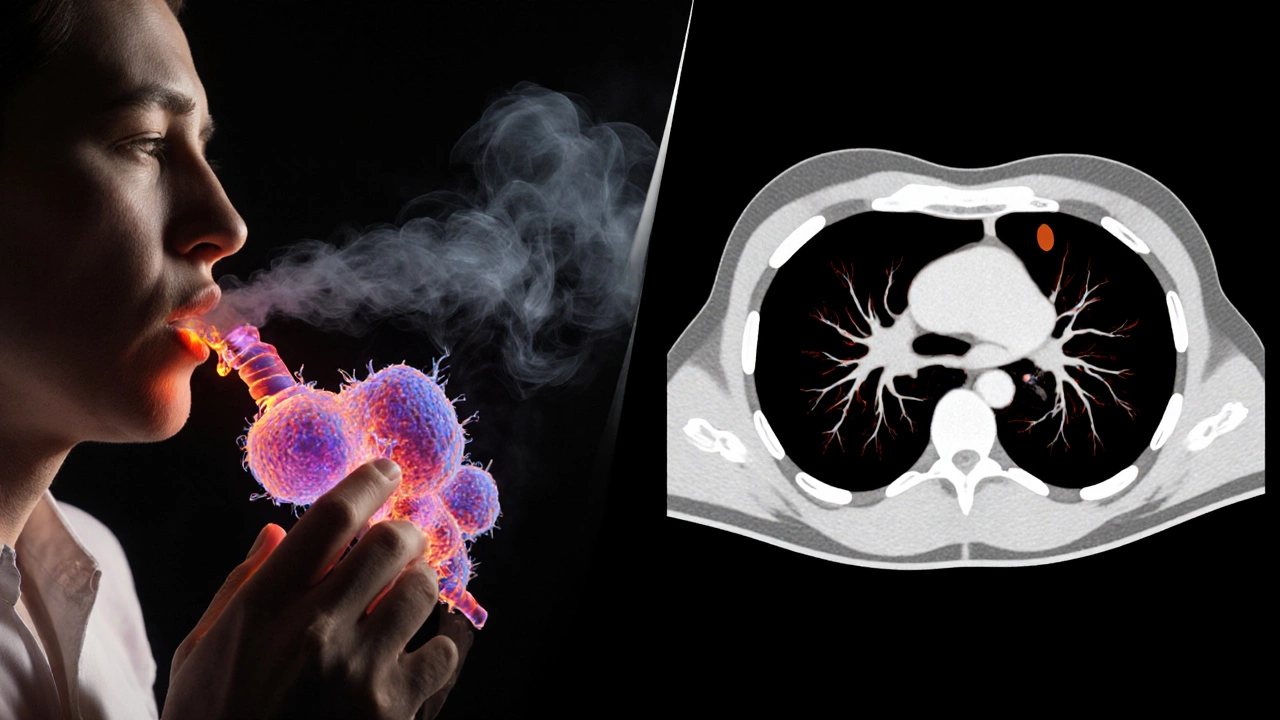

Lung Cancer: The Leading Cause of Cancer Deaths

Lung cancer is the number one cancer killer worldwide. More people die from lung cancer each year than from breast, colon, and prostate cancer combined. The biggest reason? Late detection. Most cases are diagnosed at stage III or IV, when the tumor has already spread to lymph nodes or other organs. Smoking is the top cause, but non-smokers get it too-especially in places with high air pollution or radon exposure. Even with advances in targeted therapies and immunotherapy, the five-year survival rate for advanced lung cancer is still under 10%. Early detection through low-dose CT scans can cut death rates by 20%, but fewer than 5% of at-risk adults in the U.S. and India get screened regularly.

A smoker's lungs transforming into cancer cells, with a faint CT scan showing early nodules.